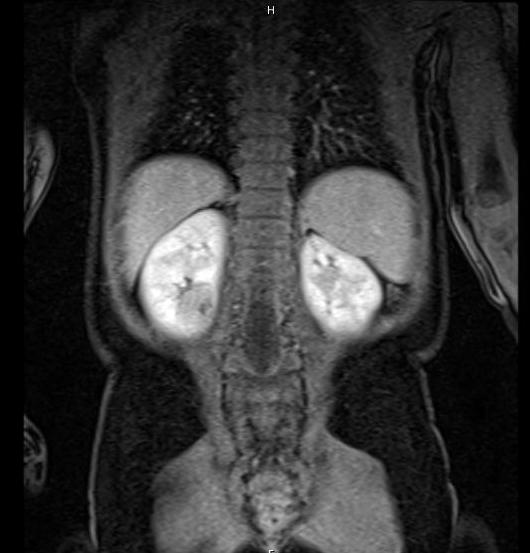

The most appropriate management of this patient with bilateral renal masses is

The next best step in management of this child with bilateral renal masses is

The guidelines from the Children’s Oncology Group call for preoperative chemotherapy when